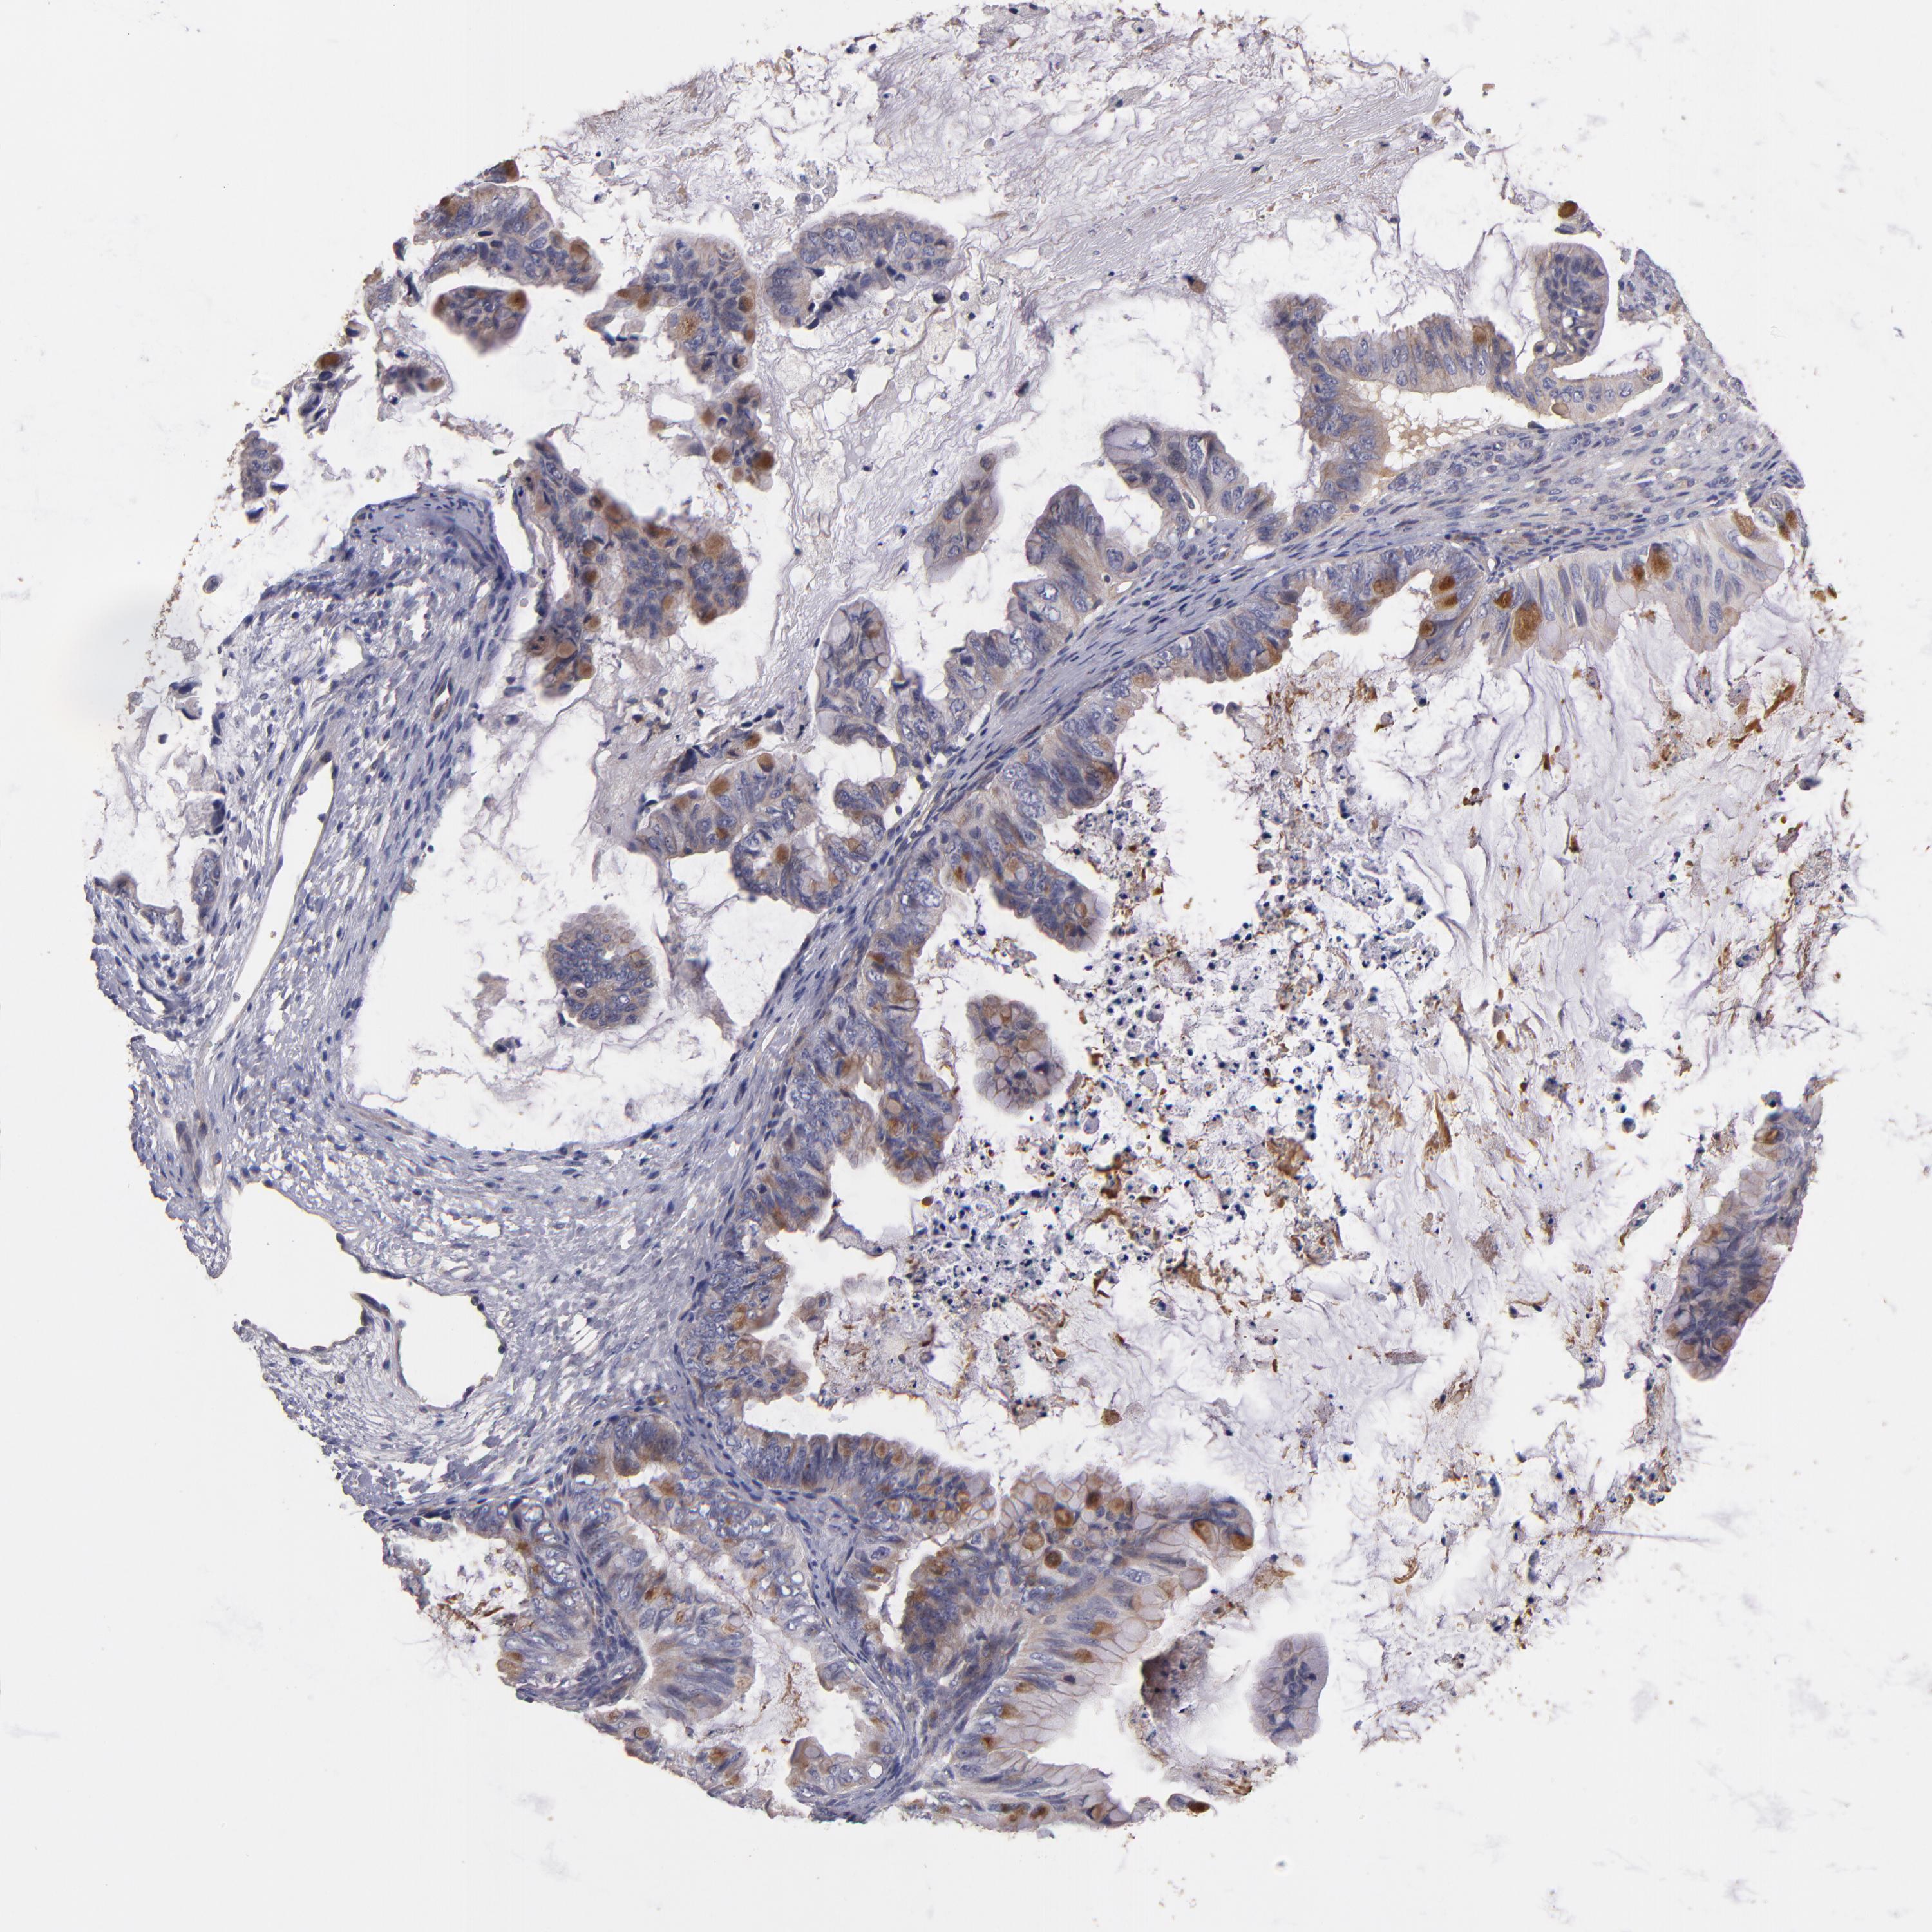

OVARIAN CANCER - Protein expressioni

A mouse-over function shows sample information and annotation data. Click on an image to view it in a full screen mode. Samples can be filtered based on level of antibody staining by selecting one or several of the following categories: high, medium, low and not detected. The assay and annotation is described here.

Note that samples used for immunohistochemistry by the Human Protein Atlas do not correspond to samples in the TCGA dataset.

Antibody stainingi

Antibody staining in the annotated cell types in the current human tissue is reported as not detected, low, medium, or high, based on conventional immunohistochemistry profiling in selected tissues. This score is based on the combination of the staining intensity and fraction of stained cells.

Each image is clickable and will lead to virtual microscopy that enables deeper exploration of all samples and also displays staining intensity scores, fraction scores and subcellular localization as well as patient and tissue information for each sample.

Antibody HPA003047

Staining

High

Medium

Low

Not detected

Intensity

Strong

Moderate

Weak

Negative

Quantity

>75%

75%-25%

<25%

None

Location

Nuclear

Cytoplasmic/membranous

Cytoplasmic/membranous,nuclear

Cystadenocarcinoma, serous, NOS

Cystadenocarcinoma, mucinous, NOS

Carcinoma, endometroid